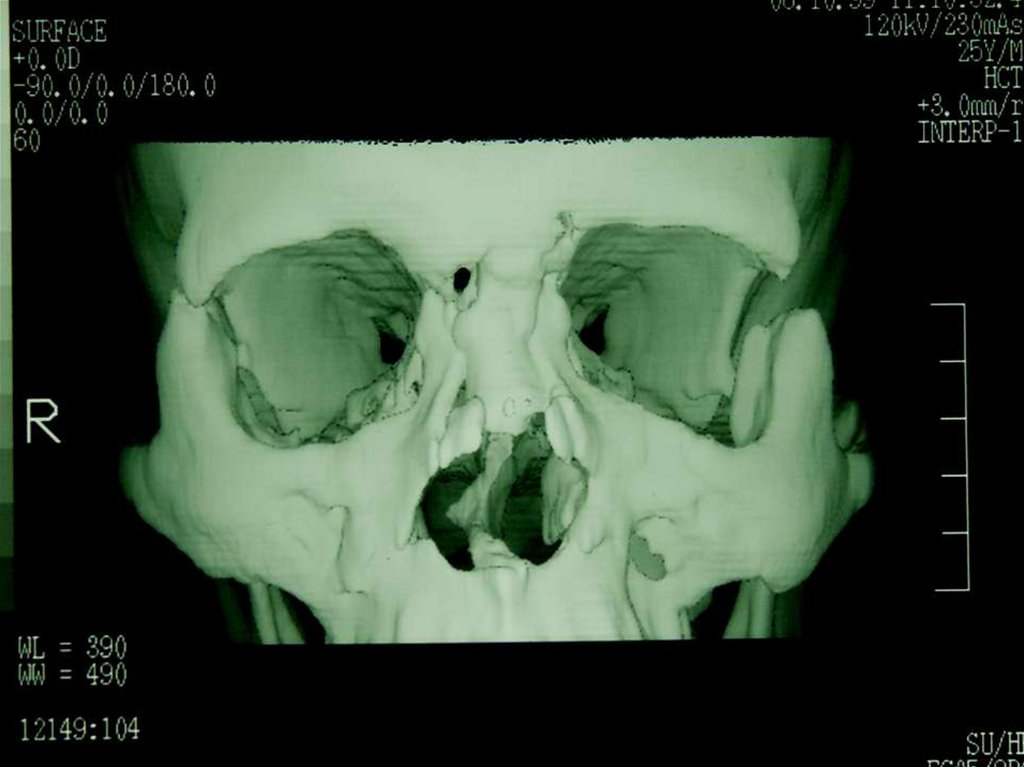

Пластика дефекта

скуловой кости

трансплантатом из

теменной области